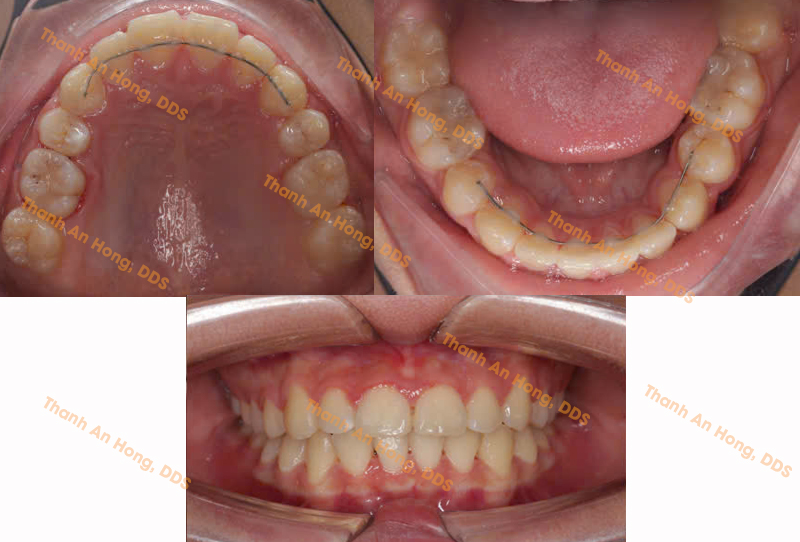

HÌNH ẢNH THỰC TẾ

Chỉnh mắc cài giảm hô